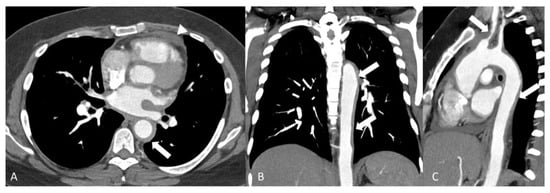

- Giannessi, C.; Smorchkova, O.; Cozzi, D.; Zantonelli, G.; Bertelli, E.; Moroni, C.; Cavigli, E.; Miele, V. Behcet’s Disease: A Radiological Review of Vascular and Parenchymal Pulmonary Involvement. Diagnostics 2022, 12, 2868. [Google Scholar] [CrossRef]